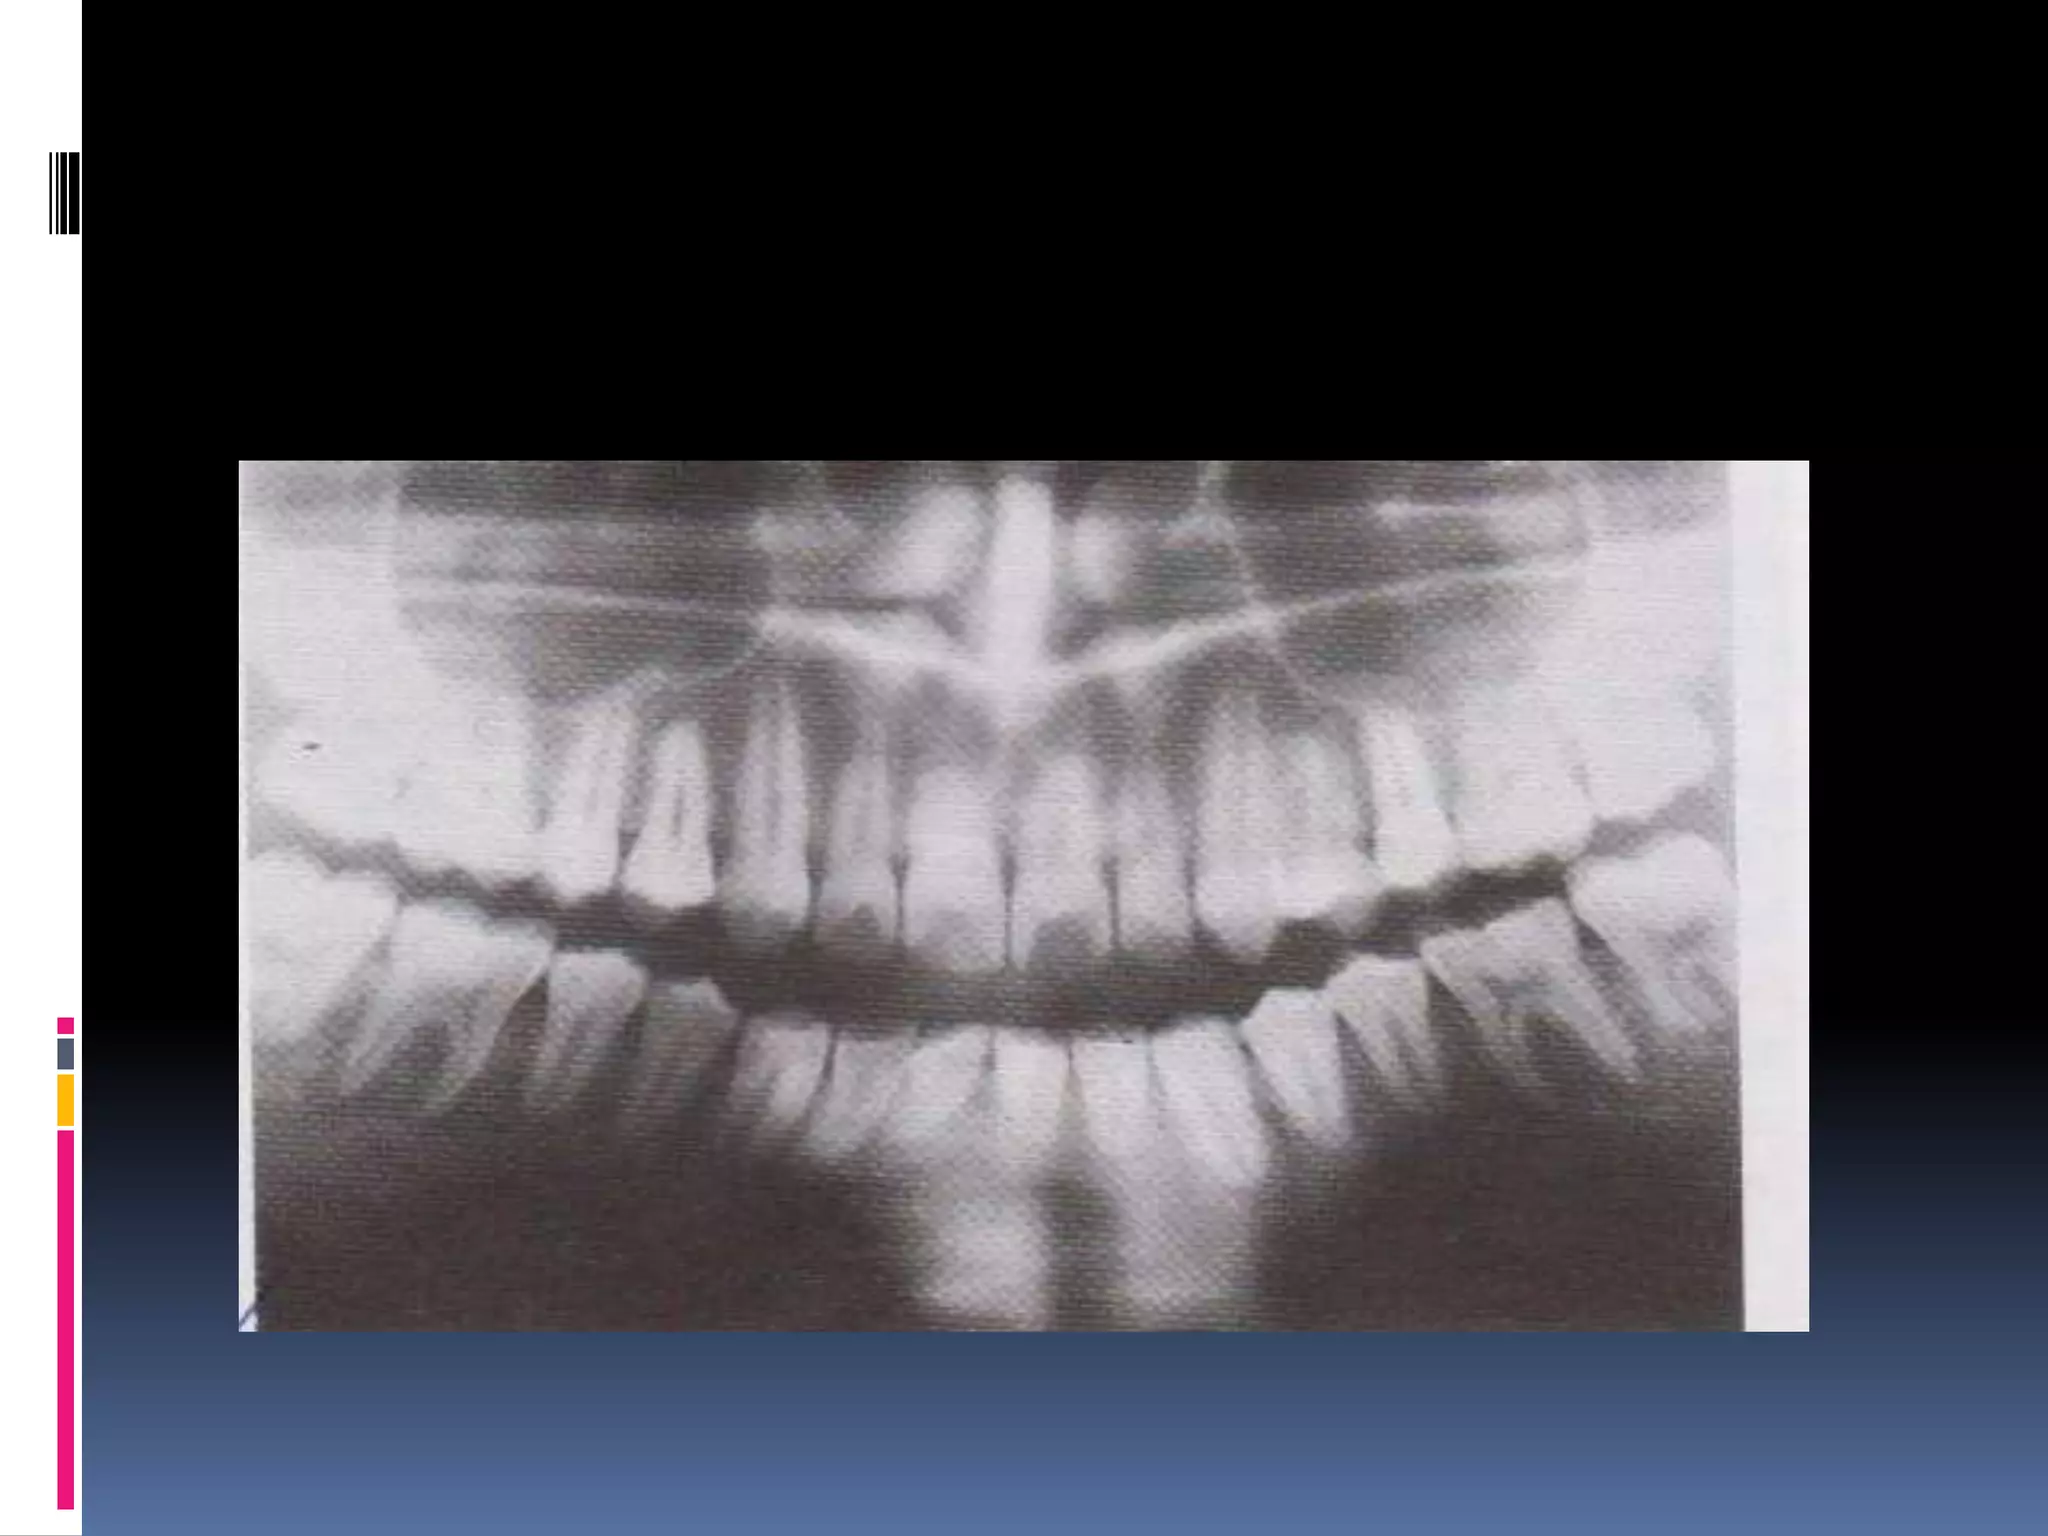

Taurodontism

 Enlagement of body & pulp chamber of

multirooted tooth , with apical displacement

of pulpal floor & bifurcation of root.

 Bull like tooth.

 Unilateral/bilateral.

 rectangular teeth with pulp chambers

increased apico occlusal height & bifucation

close to apex

Radiological features

 Rectangular shape

 Large pulp chambers with > apico occlusal

height.

 Lack of pulpal constriction ot cervical region.

 Short roots

 Bifurcation few mm above root apex.